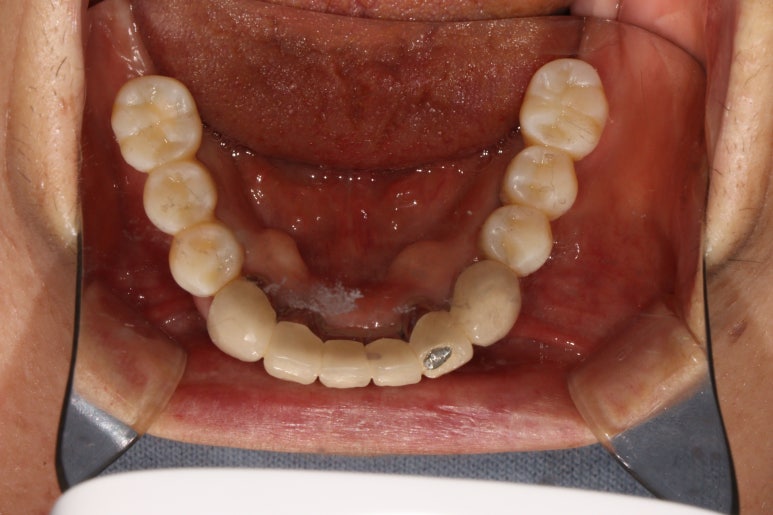

아래턱 어금니 임플란트에 임플란트 2차 수술을 시행하고나서 약 10일 뒤 실밥을 제거합니다.

이제 임플란트 인상채득을 시행합니다.

임플란트 보철물 제작을 위한 구강 스캔

각 임플란트에 연결된 치유지대주를 제거하고, 스캔 바디를 연결한 뒤 구강스캐너를 사용하여 인상채득 (뽄뜨기)을 시행합니다.

맞춤형 지대주 (custom abutment)와 임시치아를 사용한 씹기 연습.

그렇게해서 제작된 맞춤형 지대주 (custom abutment)와 임시치아를 이용하여 이제 씹는 연습을 해보시게 됩니다. 저희 치과에서는 모든 케이스에 있어 '정품 오스템 티타늄 환봉'을 사용한 맞춤형 지대주만을 사용하고 있습니다.

저희 치과와 협업하는 기공소에서 제작해온 임시치아를 장착한 상태입니다.

플라스틱 재질인 레진으로 제작되어 있어 색상은 그닥 수려하지 않으나, 연습용으로 써보기에는 아주 딱이죠?

생각보다 보기에 모양도 괜찮습니다. 요새 임플란트 보철물은 모두 CADCAM으로 지르코니아 블럭을 깎아서 제작하기 때문에, 만약 이 임시치아가 마음에 드셨다면 최종 지르코니아 크라운도 컴퓨터에 입력된 데이터를 이용하여 똑같이 깎아서 제작해드릴 수 있답니다. 이 모든게 치과에서 구강스캐너를 사용하기에 가능하죠..

어쨌든, 어금니 임플란트로 치아가 6개나 새로 제작되었기에 볼이나 혀가 씹히진 않는지 - 식사시에 아프거나 음식이 끼는 것은 없는지 등을 확인하기 위해 약 2-4주 정도 사용해보시게 됩니다.